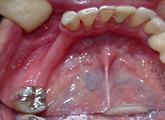

上の歯は総義歯です。

インプラントを植立しました。